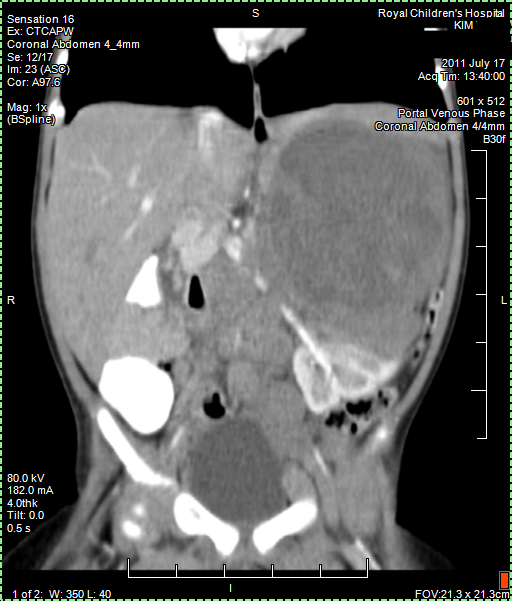

CT (CAT) scan 17July 2011